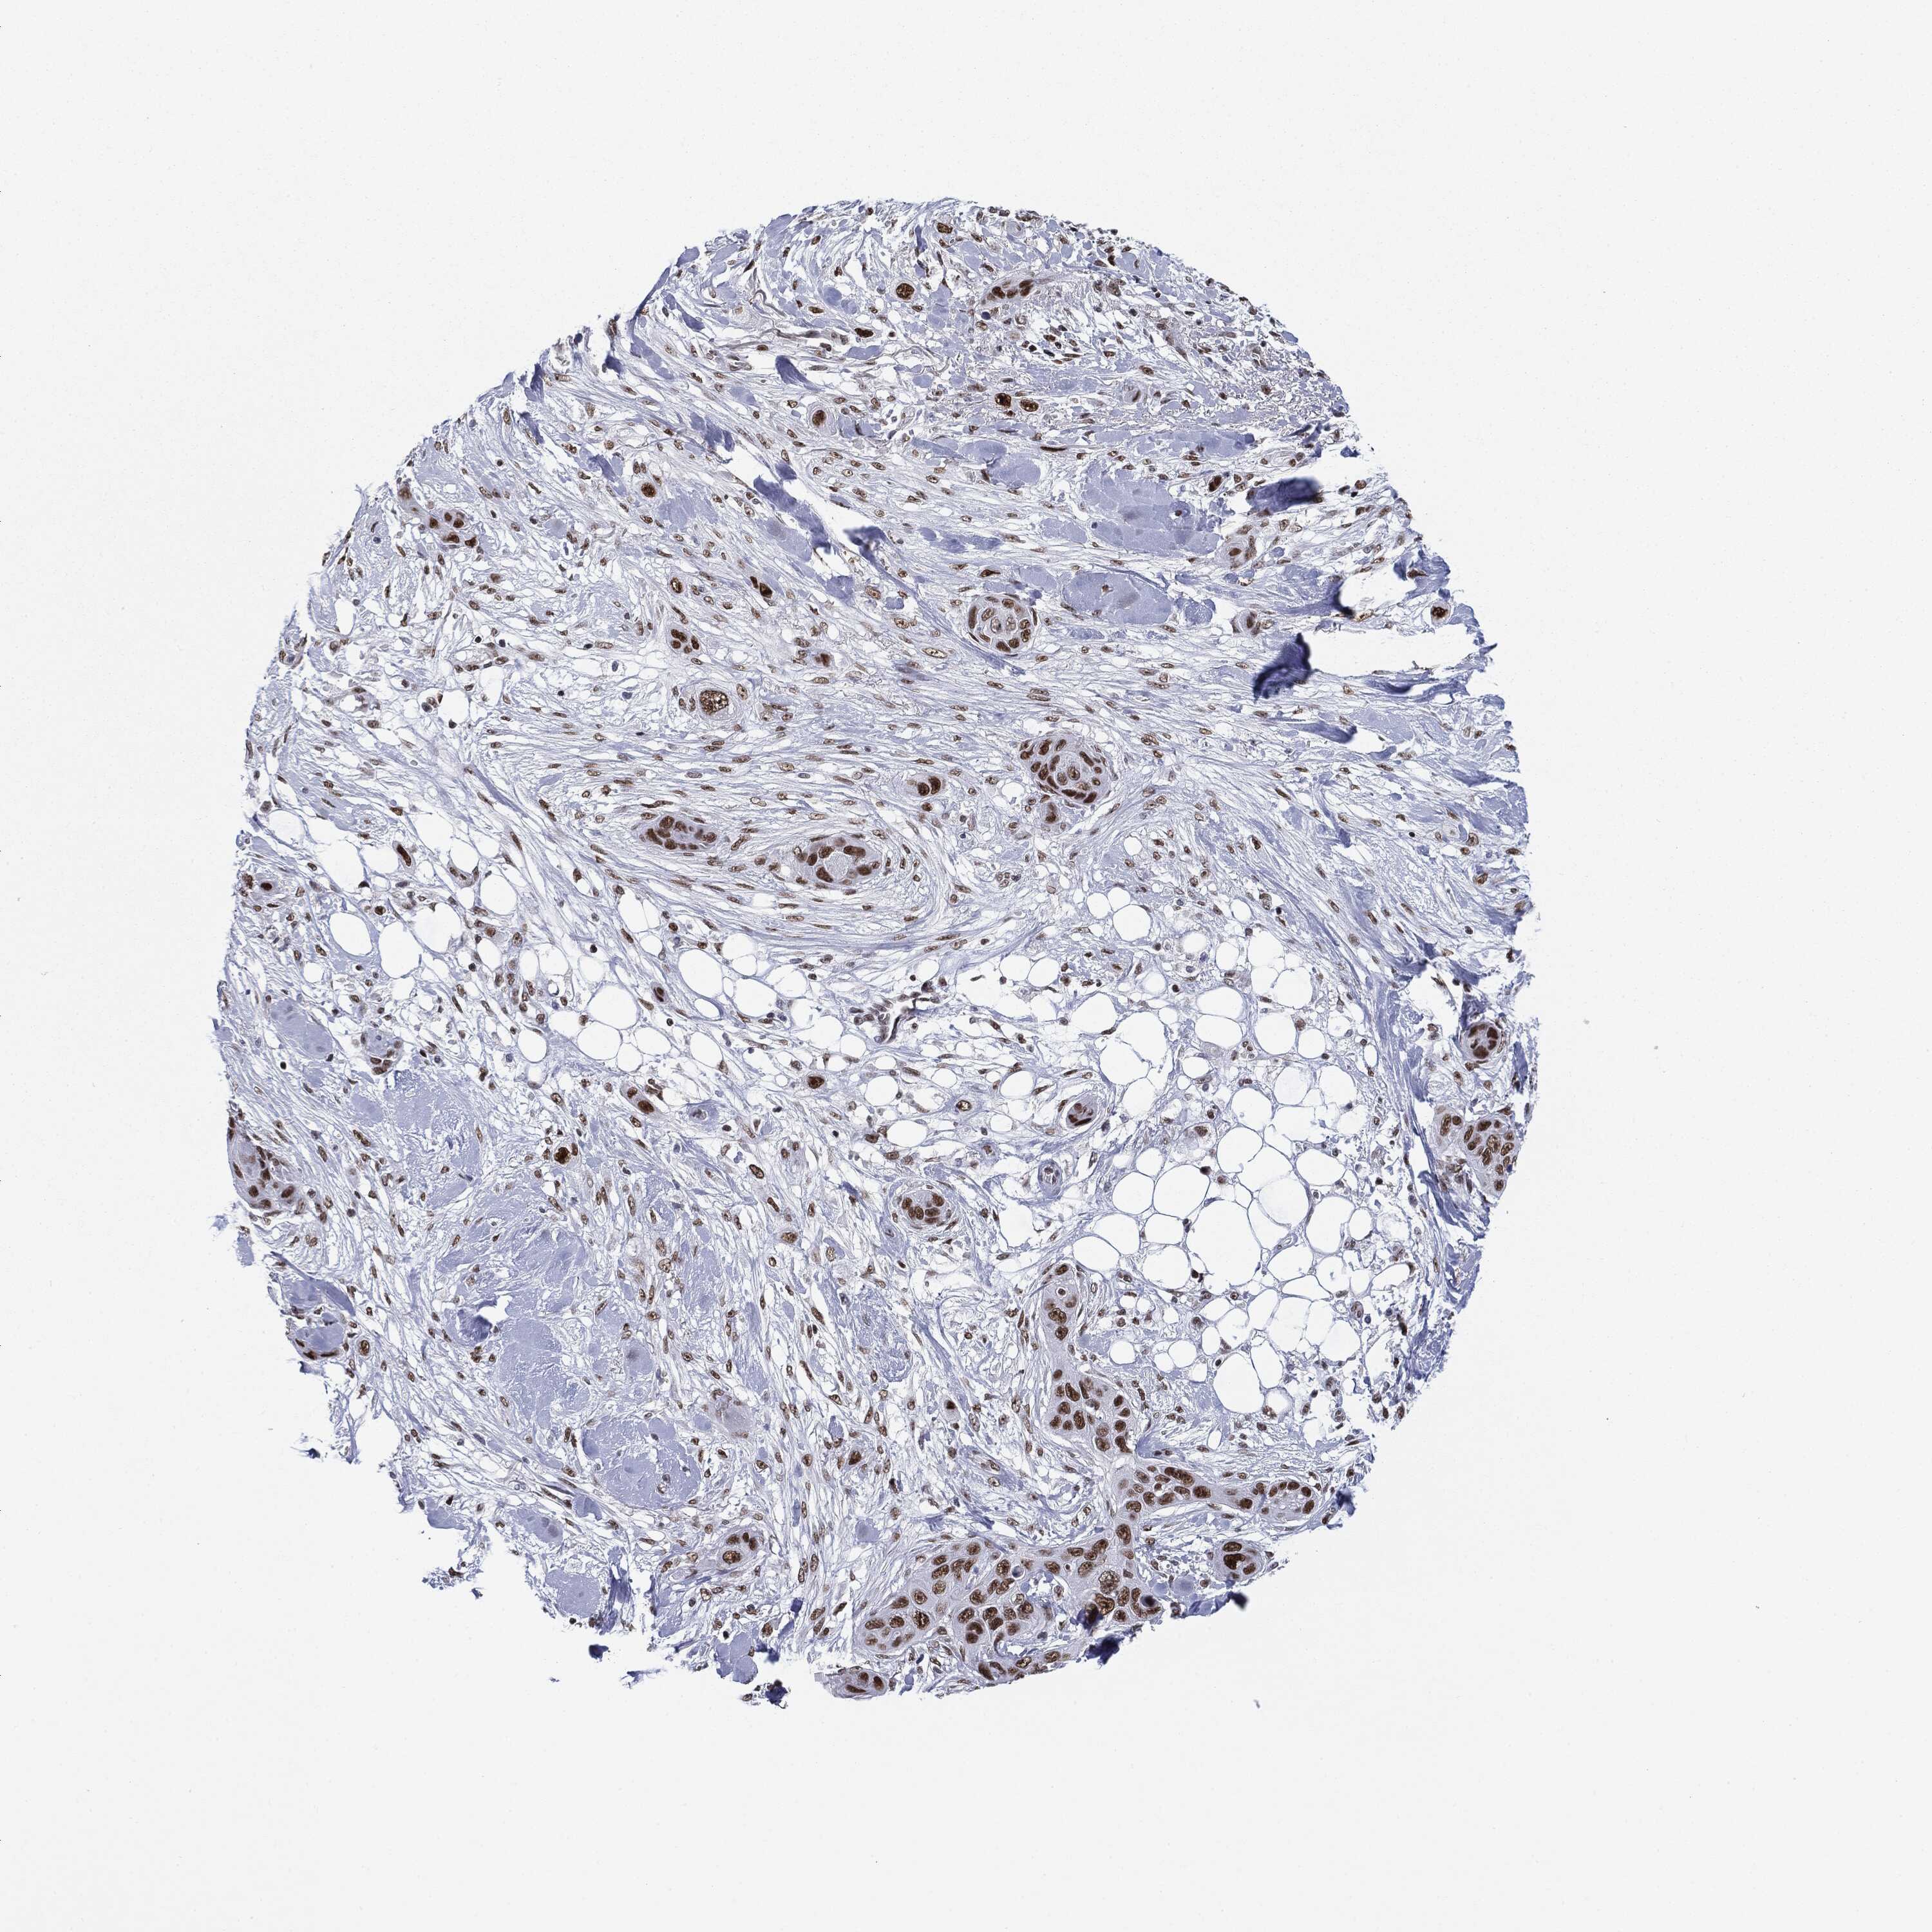

SKIN CANCER - Protein expressioni

A mouse-over function shows sample information and annotation data. Click on an image to view it in a full screen mode. Samples can be filtered based on level of antibody staining by selecting one or several of the following categories: high, medium, low and not detected. The assay and annotation is described here.

Antibody stainingi

Antibody staining in the annotated cell types in the current human tissue is reported as not detected, low, medium, or high, based on conventional immunohistochemistry profiling in selected tissues. This score is based on the combination of the staining intensity and fraction of stained cells.

Each image is clickable and will lead to virtual microscopy that enables deeper exploration of all samples and also displays staining intensity scores, fraction scores and subcellular localization as well as patient and tissue information for each sample.

Antibody CAB080116

Staining

Medium

Intensity

Moderate

Quantity

75%-25%

Location

Cytoplasmic/membranous

Basal cell carcinoma